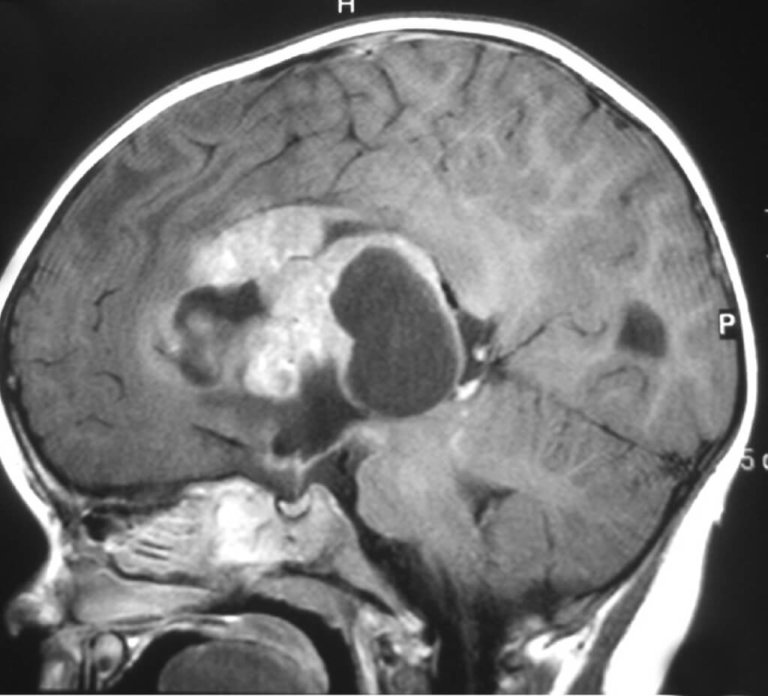

Brain Tumour Category : Tumeurs cérébrales pédiatriques

Médulloblastome Featured Image

Médulloblastome

Astrocytome pilocytique Featured Image

Astrocytome pilocytique

Épendymome Featured Image

Épendymome

Craniopharyngiome Featured Image

Craniopharyngiome

Tumeur teratoïde/rhabdoïde atypique (TT/RA) Featured Image

Tumeur teratoïde/rhabdoïde atypique (TT/RA)

Gliomes du tronc cérébral Featured Image

Gliomes du tronc cérébral

Gliome des voies optiques Featured Image

Gliome des voies optiques